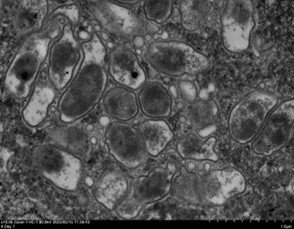

<新しく発見されたリケッチアの蛍光染色および電子顕微鏡写真>

|

![]() |